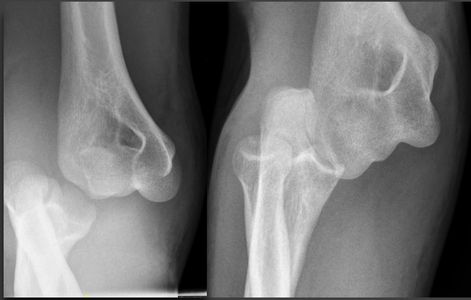

Case example - 20 year old female fell 2m onto crash mat in gym. Elbow in flexion, hand/wrist impact on mat.

XR image shows lateral, AP and oblique views.